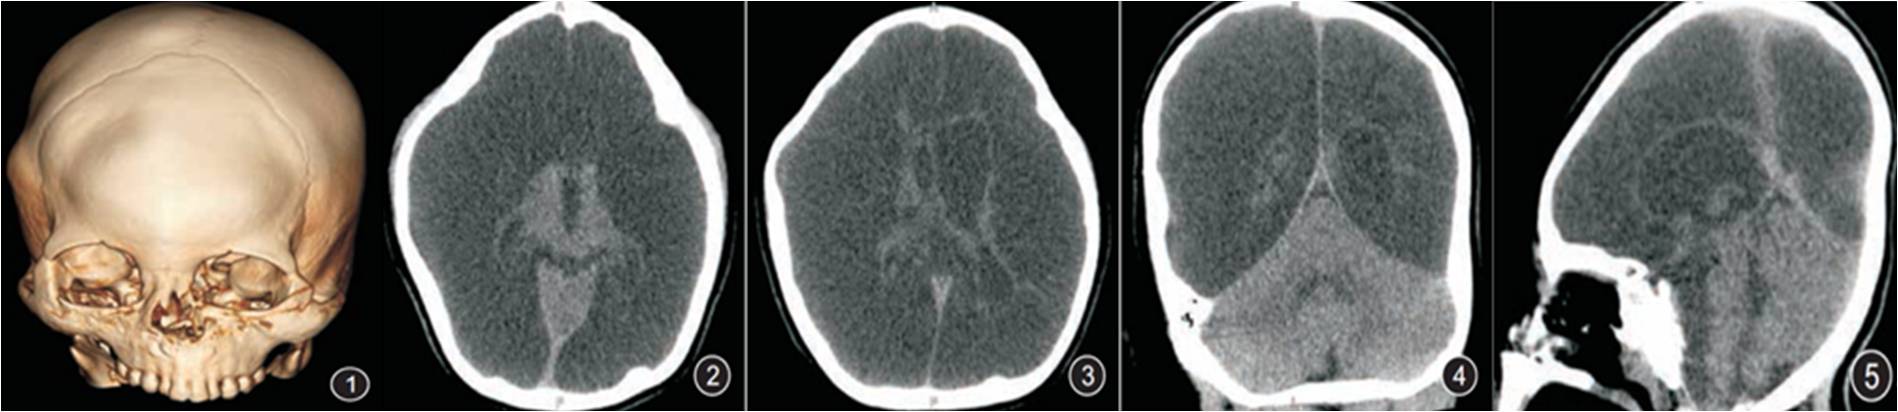

男,3歲,積水型無腦畸形。圖1 CTVR顯示頭顱增大,顱縫及囟門均已閉合;圖2~5軸位結(jié)合冠、矢狀位重建顯示:雙側(cè)大腦半球缺如,代之為大量腦脊液密度影,僅見部分基底節(jié)及丘腦存在。側(cè)腦室及第三腦室存在、輕度擴張。大腦鐮存在,前部部分缺如。小腦幕完整存在及幕下結(jié)構(gòu)完好。